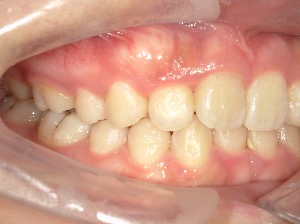

after

患者さんの年齢 20代 女性 症状 ガタガタを治したい 治療内容 マウスピース矯正治療 費用 90万(税抜) 治療期間・回数 治療期間2年、通院回数10回 メリット 笑顔が綺麗 デメリット・リスク 期間がかかることがある - マウスピース矯正